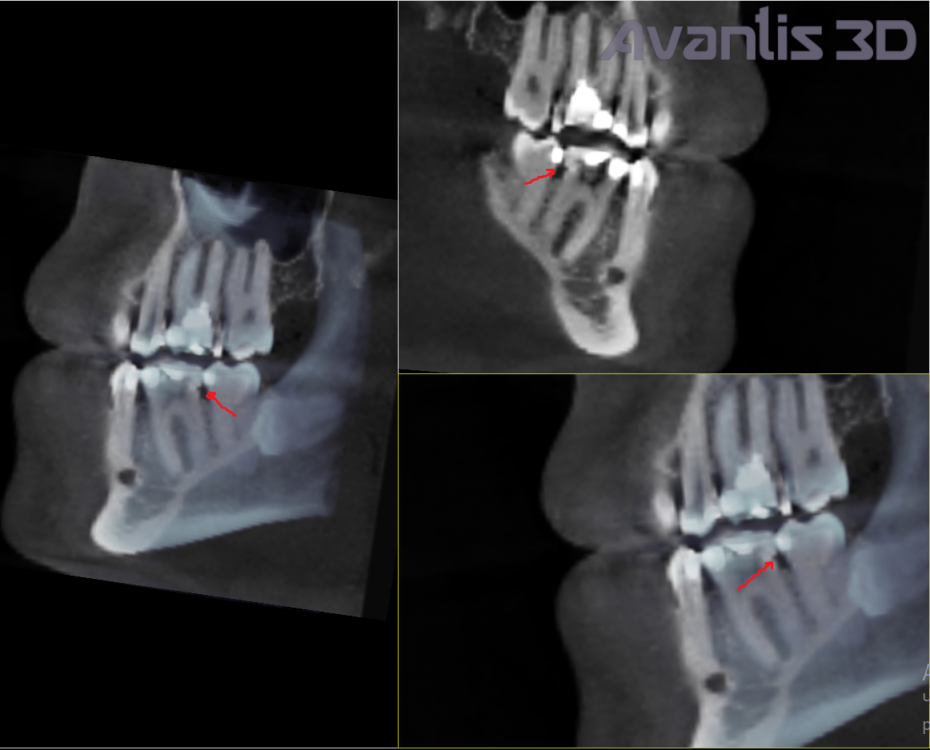

amkazan Опубликовано 14 июля, 2022 Поделиться Опубликовано 14 июля, 2022 Здравствуйте, между 6 и 7 зубом слева появилась чувствительность на воду комнатной температуры. Боль не ужасная, но скорее ощущение весьма чувствительное, проходит через некоторое количество секунд 1) Сначала думал из-за кариеса в 7ке. Залечили. Не прошло 2) Потом подумал что из-за зуба мудрости 8ки горизонтального. Удалили. Не прошло 3) Потом уже обратился к КТ и вот смотрю : Может ли это быть из-за некой полости или некой трещины в 6ке, которая указана стрелочками на 2х приложенных скриншотах? (Я не стоматолог, что сам принимаю решения как мне лечиться. Просто ситуация сложилась такая, что я постоянно перемещаюсь по городам и не могу лечиться у одного стоматолога и поэтому приходится самому пытаться разбираться и просить помощи по совету) Прошу у вас помощи.?Разобраться Прикладываю КТ (это был Vatech, думаю Pax-i3D как самый распространённый, но не факт) в формате DCM на google диске и на Яндекс диске https://drive.google.com/file/d/1vPTicAzKgWuJWQIRL_fG968K7VONyEou/view?usp=sharing https://disk.yandex.ru/d/3vmKZGk3sydIqw p.s. Заодно хочу спросить вопрос а что это за полость под 5кой??? Смотрю на снимки от 2018го. Она там уже есть. Была ли раньше неизвестно.. Ссылка на комментарий

Женька Опубликовано 14 июля, 2022 Поделиться Опубликовано 14 июля, 2022 Здравствуйте. Полость под 5-выход из костной ткани ментального нерва (нормальная анатомия, делать ничего не нужно с этим) Ваш 6 практически полностью состоит из пломбы, надо как минимум проверить прилегание этих самых пломб. Ну и пожалуй закрыть его коронкой, чтобы не сломался глубже и безвозвратно. Боли могут быть как раз следствием выше сказанного. 1 1 Ссылка на комментарий